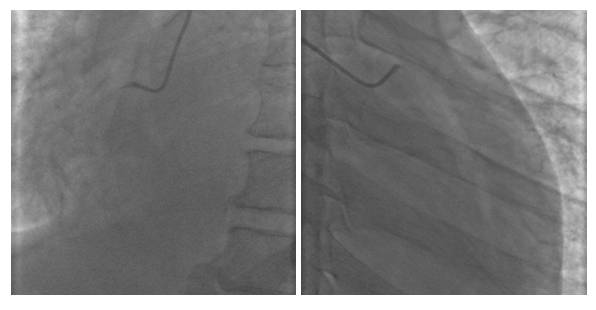

12-20 冠脉造影+PCI术